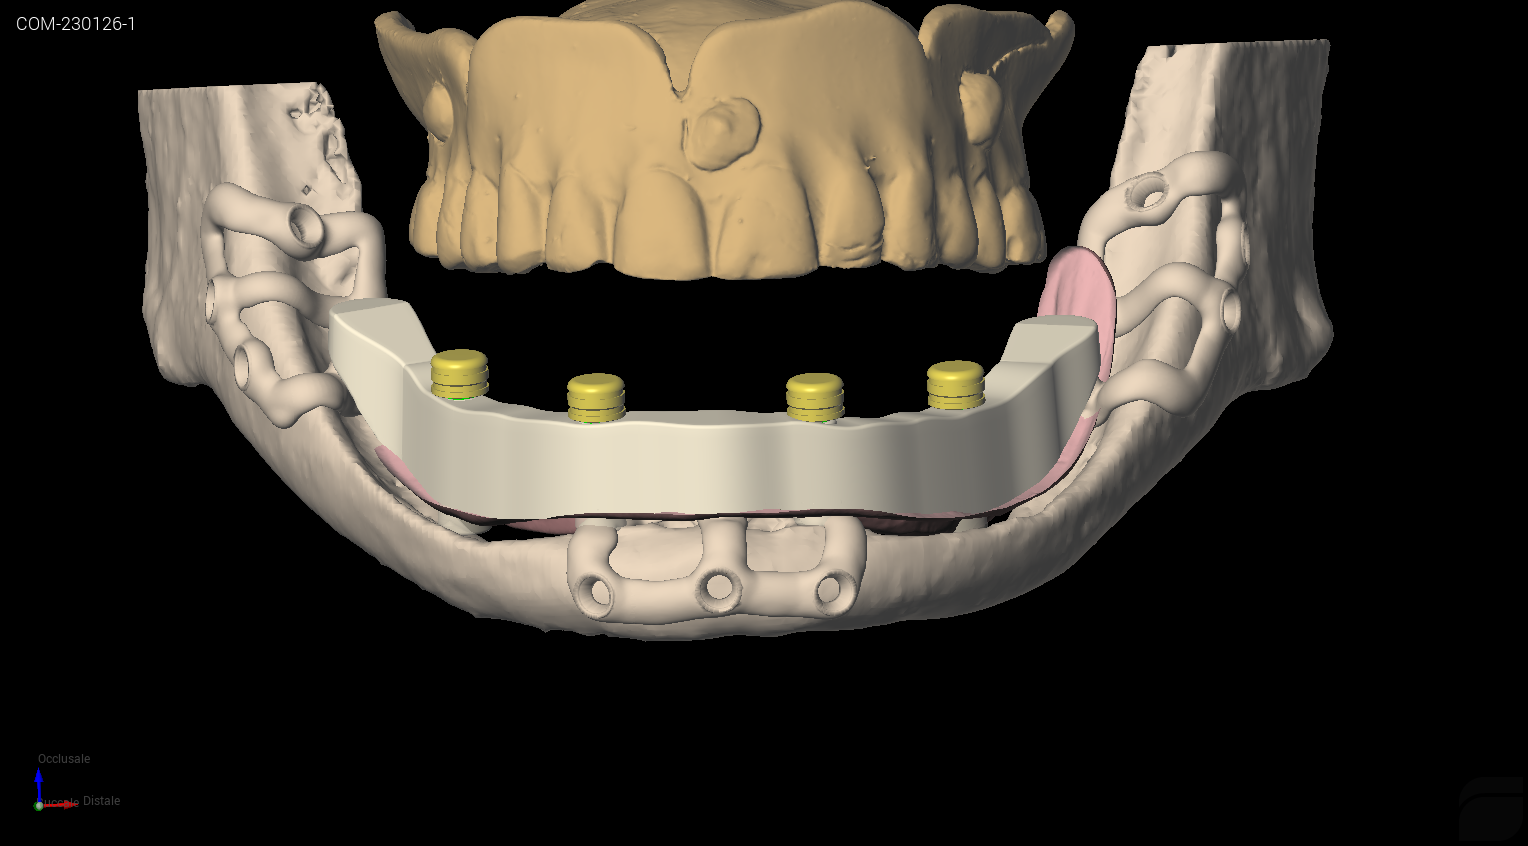

Il dispositivo prevede dunque tre punti di appoggio osseo stabilizzato a mezzo viti di sintesi (diametro 2 mm, lunghezza 6mm autofilettanti) e contestualmente tre emergenze, congiunte ad una barra extramucosa che funge da struttura di sostegno della contro-barra fresata rimovibile (fig. 3a, b, c), a sua volta ancorata ad attacchi a sfera. Contestualmente alla progettazione dell’impianto iuxta osseo, l’Odt. Fabio Marchiori, ha provveduto alla progettazione della parte protesica del dispositivo. Si è trattato, nello specifico, come appena descritto, di una controbarra ibrida: l’anima della struttura è stata progettata e stampata in titanio medicale (mediante tecnica SLM con Ti grado 23) e la componente anatomica è stata fresata da un disco di composito. La controbarra viene ancorata alla barra portante dello iuxta osseo per mezzo dei già citati attacchi a sfera, che sono stati avvitati per mezzo di filettatura dell’impianto stesso.

Posizionamento digitale attacchi a pallina

Fig. 3(c). Posizionamento digitale attacchi a pallina.

La scelta di una protesi overdenture (o protesi rimovibile) è stata determinata da una doppia necessità: consentire alla paziente una corretta igiene del dispositivo e controllare regolarmente lo stato della mucosa nelle sedi di emergenza dell’impianto, al fine di evitare peri-implantiti ed esposizione del manufatto. Validate le scelte progettuali da parte dell’Operatore (Dr. Francesco Grecchi), si è proceduto alla realizzazione dell’impianto iuxta osseo per mezzo di un processo additivo, comunemente noto come stampa 3D: il materiale d’elezione è il Titanio grado 23, noto come lega di titanio medicale. Il dispositivo è stato poi ripreso con un processo meccanico di fresatura che ha consentito la realizzazione dei filetti M2 necessari per l’avvitamento delle sfere ritentive (fig. 4, 5). È seguita infine una fase di lavaggio e decontaminazione e confezionamento dell’impianto iuxta osseo secondo le procedure previste in caso di prodotti metallici impiantabili avviati a successiva sterilizzazione in autoclave.